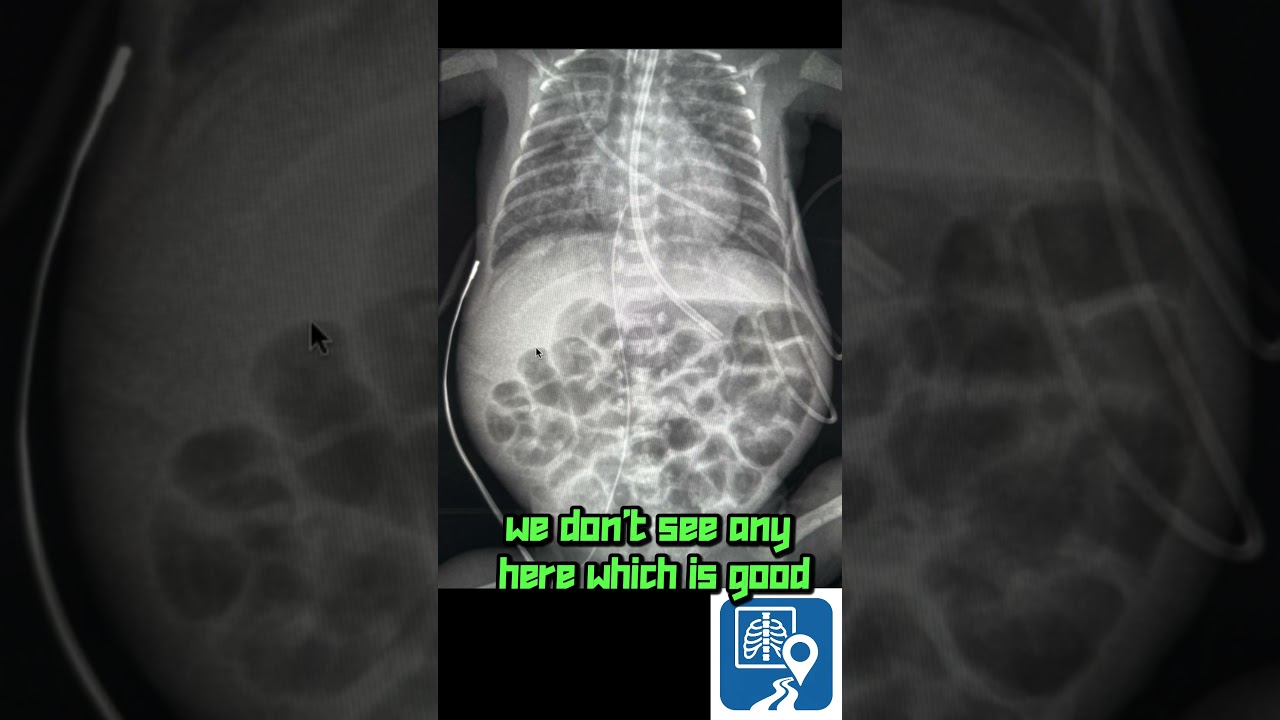

Can you spot the key findings on this newborn chest & abdomen X-ray? In under 30 seconds, we cover:

• A – Abdomen: Free air, organ silhouettes & bowel gas patterns

• T-Bones – Bony Thorax: Ribs, clavicles & vertebrae review